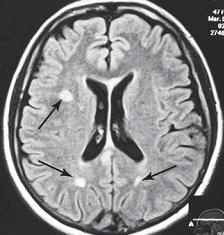

Однако меня не удовлетворили результаты его обследования. Если бы дело было только в грыжах, это полбеды. Меня смущало наличие других симптомов, которые косвенно свидетельствовали о возможном поражении ЦНС. Поэтому я послал его на дополнительные обследования МРТ головного мозга (№ 33), тесты (ИФА (иммуноферментный анализ), ПЦР (Полимеразная Цепная Реакция на инфекции), которые дали положительный результат на герпесвирусы: Epstein-Barr virus (EBV) (вирус Эпштейна-Барр) и Cytomegalovirus (CMV) (вирус Цитомегаловирус).

МРТ № 33

МРТ № 33 На МРТ отчётливо видны множественные очаги демиелинизации, вследствие развития нейроинфекции